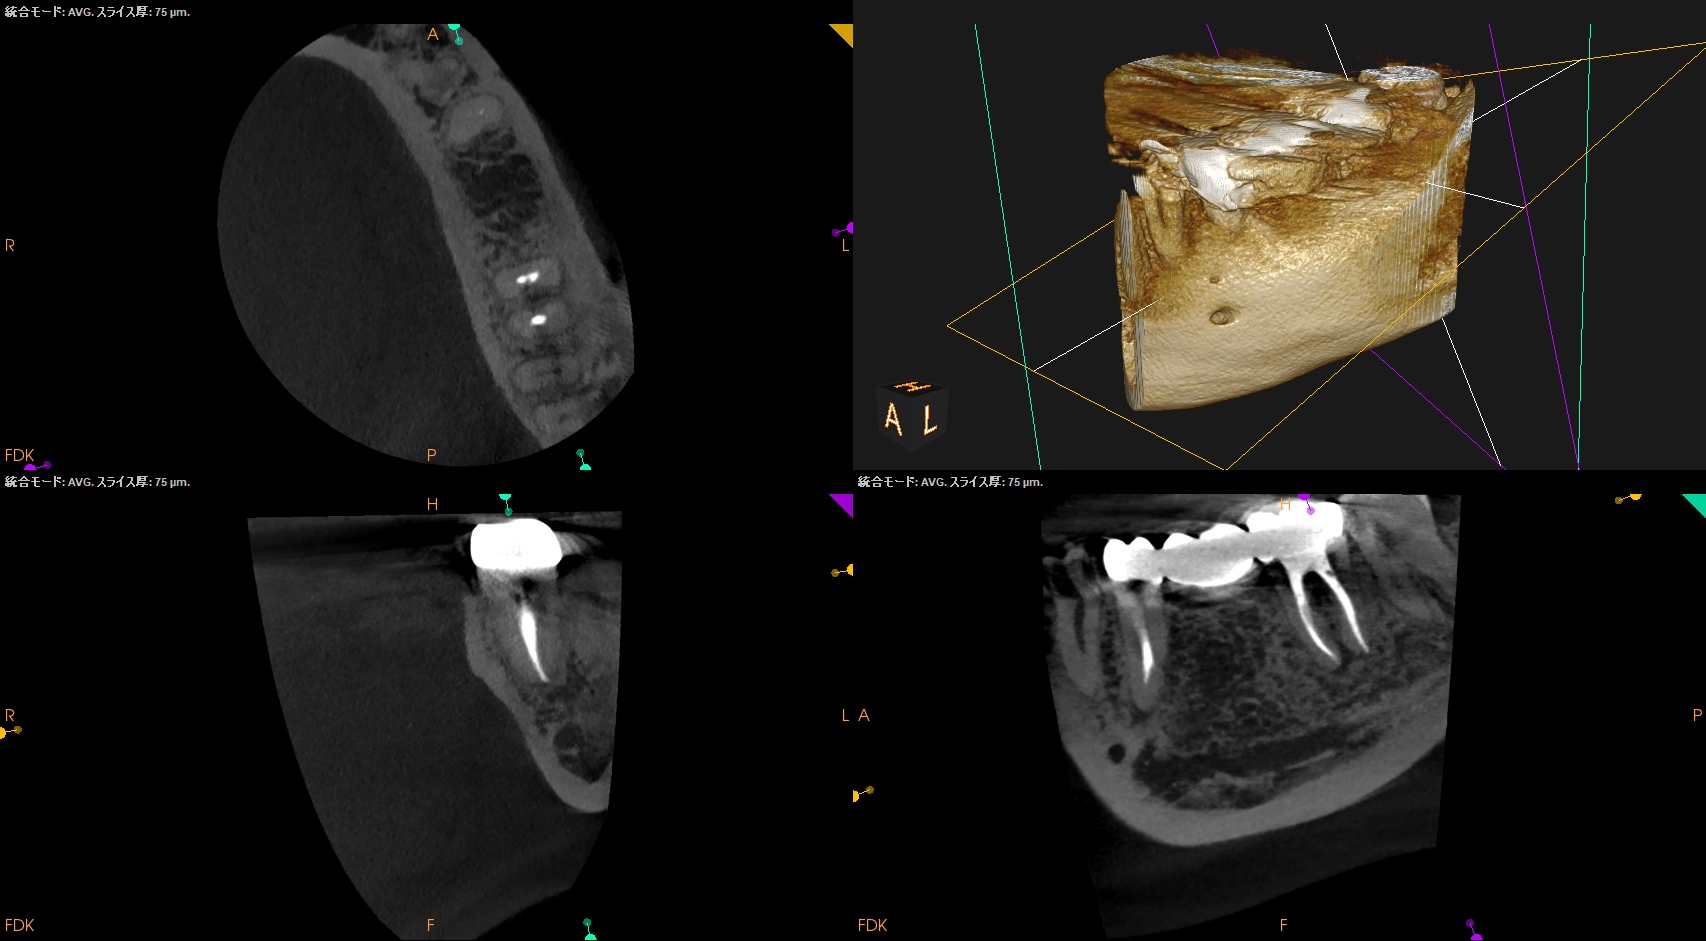

Post-op 1yr recall(2025.1.29)

MB

ML

D

初診時と比較した。

大きく状況は改善された。

ということで経過観察も終了でいいだろう。